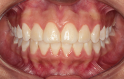

Classe II div 1, articulé croisé postérieur, surplomb accru, déviation de la ligne médiane maxillaire, rotations d'encombrement

État initial

État final

Résultats obtenus

- Relation de classe I obtenue

- Guidage fonctionnel des canines des deux côtés

- Articulé postérieur corrigé

- Surplomb et recouvrement normaux obtenus

- Surplomb amélioré

- Lignes médianes coïncidentes

- Bonne inclinaison axiale des incisives

- Courbe de Spee nivelée

- Forme de l'arcade améliorée

- Cas où tous les objectifs du traitement ont été atteints

- Des arcades harmoniques ont été obtenues